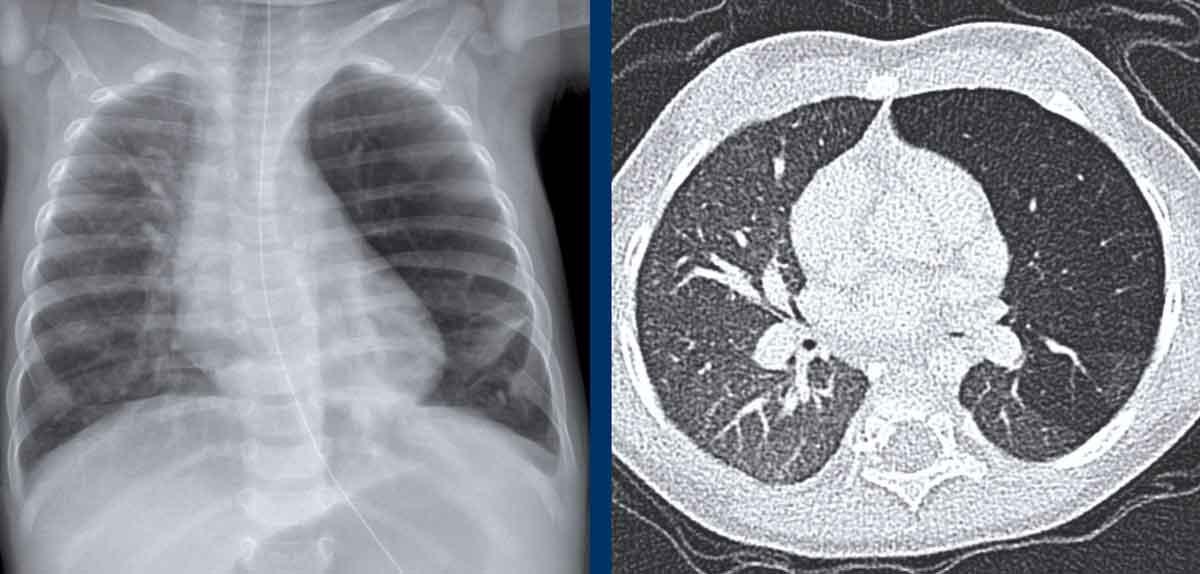

Hình ảnh của một trẻ sơ sinh, 40 tuần tuổi thai.

Nghi ngờ trước sinh có CPAM lớn ở bên trái.

Lúc sinh có suy hô hấp

Hình ảnh

Phim X-quang cho thấy một tổn thương mờ đục hình tròn lớn.

Di lệch nặng các cấu trúc đường giữa kèm xẹp phổi phải.

Ống nội khí quản ở vị trí sâu. Ống thông dạ dày tại chỗ.

Do cần can thiệp trực tiếp, CT có tiêm thuốc cản quang tĩnh mạch đã được thực hiện.

CT cho thấy một tổn thương dạng nang lớn ở thùy trên phổi trái, với sự di lệch của các cấu trúc mạch máu và phế quản.

Tổn thương không có liên quan đến bất kỳ mạch máu hệ thống nào, điều này loại trừ khả năng phổi biệt lập.

Đây là CPAM (dị dạng tuyến nang bẩm sinh của phổi), chưa được thông khí.